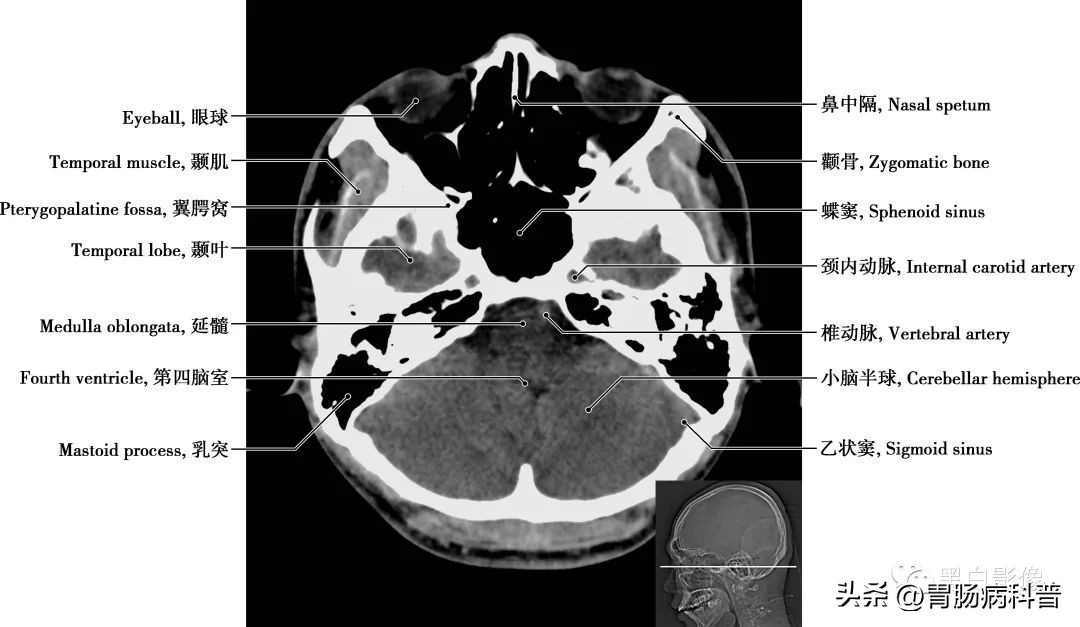

图1-1-16 经第四脑室侧孔轴位切面

翼腭窝 位于颞下窝前内侧,上颌骨(或上颌窦后壁)与翼突之间,前界为上颌骨,后界为翼突及蝶骨大翼前界,顶为蝶骨体下面,内侧壁为腭骨的垂直部。窝内有颌内动脉、上颌神经及蝶腭神经节。翼腭窝向外经翼上颌裂通颞下窝,向内上经蝶腭孔通鼻腔,向前经眶下裂通眼眶,向后上经圆孔通颅中窝,借翼管通颅底外面,向下移行于腭大管、腭大孔通口腔

图1-1-17 经第四脑室正中孔轴位切面

延髓 居于脑的最下部,与脊髓相连,上接脑桥,其主要功能为控制基本生命活动,如控制呼吸、心跳、消化等。延髓向下经枕骨大孔连接脊髓。乳突 位于鼓室的后下方,为外耳门后方的骨性突起,含有许多大小不等的气房,称乳突小房,各气房彼此相通,与鼓室之间的鼓窦相通